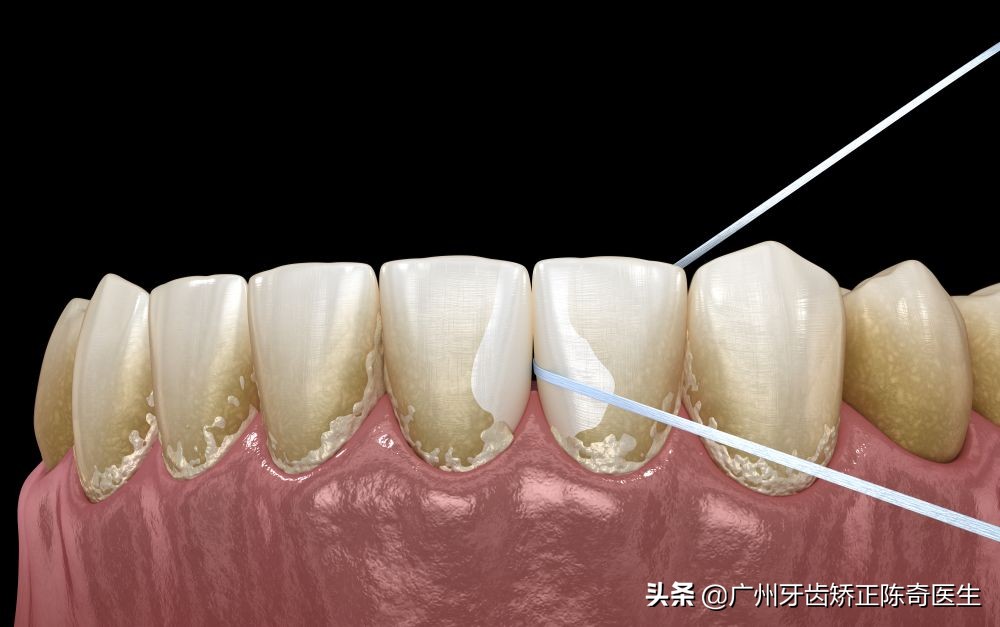

牙结石从软垢,逐渐钙化变硬附着在牙齿表面,成分有磷酸钙、水、碳酸钙等等。通常存在于唾液腺开口处的牙齿表面。如下颚前牙的舌侧表面,上排后牙的表面和牙齿颈部等等。

牙结石最开始是乳白色的软垢,通过钙化变硬后,越来越多,会呈现出黄色、棕色,或黑色等,有些与自然牙颜色相近,有的则明显可见差异。

作为口腔健康的一级杀手,牙结石的存在不容忽视。值得注意的是,在牙结石形成之初由于硬度较小,使用口腔清洁或刷牙等方法往往较容易清除,而随着日积月累的钙化、牙结石在口腔中紧密附着,普通的刷牙或口腔清洁方法便难以将其去除了。